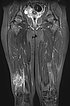

Coronal fat-suppressed T2-weighted MRI of the thighs shows an intramuscular venous malformation on the right thigh (hyperintense).

Axial T2-weighted MRI, fat-suppressed, shows the close relationship to the periosteum of the femur. This location is particularly painful due to inflammatory irritation of the periosteum.

T2-weighted MRI without fat suppression in the axial plane reveals inflammatory, fibrotic remodeling of the lesion due to multiple inflammations. The right vastus lateralis of the quadriceps femoris muscle is completely penetrated by the lesion.

Dynamic MR angiography 62 s after injection of the contrast agent shows slow pooling of the contrast agent in the lesion without early venous return (slow-flow malformation). The lesion is connected to the deep conducting vein system (communicating veins).

The VM completely enhances contrast media (MRI, T1-weighted, fat-saturated). This makes the differential diagnostic consideration of a lymphatic malformation redundant.